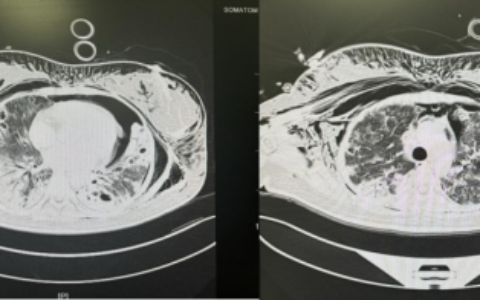

基于对鼻内镜手术技巧的深刻理解与鼻面部周围解剖结构的精准掌握,邓晓聪在全面评估病情及充分了解患者诉求后,决定突破常规术式局限,创新性运用高清鼻内镜微创技术,经鼻腔自然通道精准取出肿瘤。

首先定位难。需要主刀医生对复杂面部结构了然于心,才能精准掌握肿瘤边界,明确肿瘤组织分离范围,稍有偏差可能无法完整切除病灶,留下复发隐患;

其次是风险高。肿瘤所在位置,神经血管密布,伤及正常组织,可能引发术后面部神经麻木或供血障碍,形成并发症;

再是操作难。要在狭窄的鼻腔自然通道内精准剥离肿瘤组织,犹如村道上开赛车,稍有不慎,手术将前功尽弃。

邓晓聪凭借二十多年深厚的鼻内镜微创手术功底,仅用40余分钟,便成功完成了创新手术入路的“保面”手术,完整切除了肿瘤,患者面部没有一点手术痕迹,鼻腔也和术前一样没有不适感。